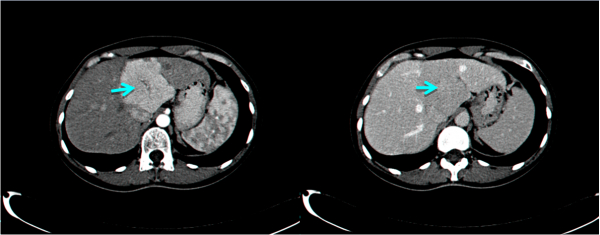

בבדיקות מעבדה: תפקודי הכבד לרוב תקינים, אך תיתכן עליה קלה ברמת האנזימים. האבחנה מתבצעת על ידי טומוגרפיה ממוחשבת (תמונה 26.10 ) או תהודה מגנטית (תמונה 27.10) כך שבדרך כלל אין צורך לקחת ביופסיה. באולטרה-סאונד ניתן להדגים גוש בכבד (תמונה 28.10).

| |

| תמונה 8.10: FNH משמאל מראה השאת בניתוח (חץ). מימין FNH לאחר הוצאתו מהכבד. למטה חתך מאקרוסקופי של הגוש. | |